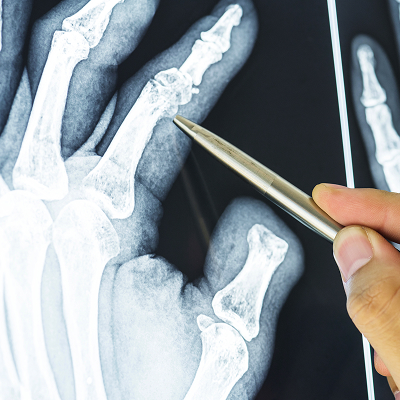

Методы диагностики

Для постановки точного диагноза используется:

• Осмотр травматолога. Врач оценивает положение пальца, наличие отека, подвижность суставов

• Рентгенография. Основной метод, позволяющий увидеть линию перелома и смещение

• Компьютерная томография (КТ). Применяется при сложных, оскольчатых переломах фаланги

• МРТ кисти. Помогает выявить повреждения мягких тканей и связок

По результатам диагностики врач решает, достаточно ли наложения гипса или требуется хирургическое вмешательство.